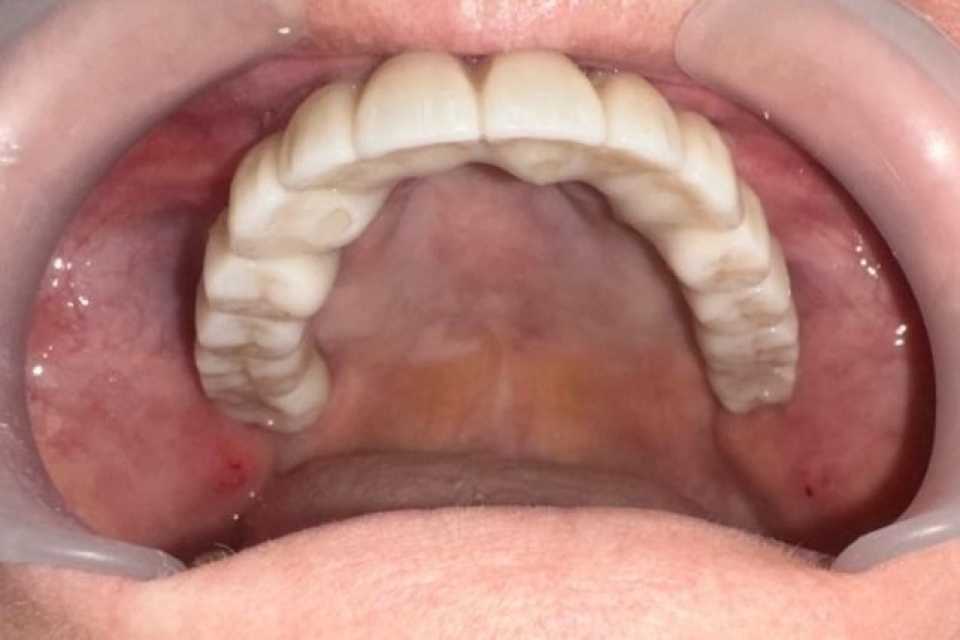

Sub anestezie generală s-au inserat 4 implanturi zigomatice și 2 implanturi pterigoide și 1 implant dentar normal cu ajutorul cărora am realizat o lucrare dentară protetică fixă din ceramica pe zirconiu insurubabila de 14 elemente.